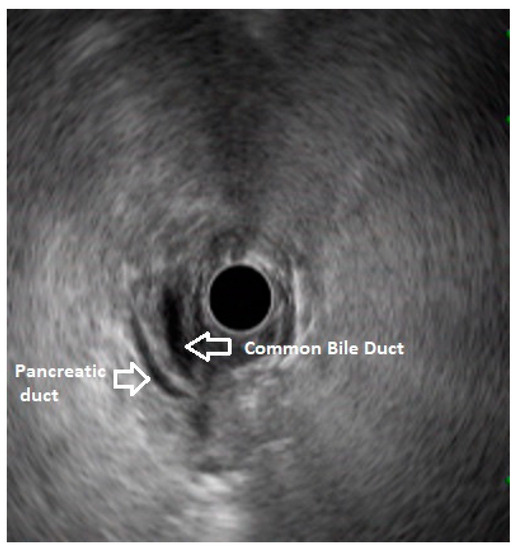

5. Pancreas Divisum

6. Endoscopic Ultrasound Features of Pancreas Divisum: Radial and Linear EUS